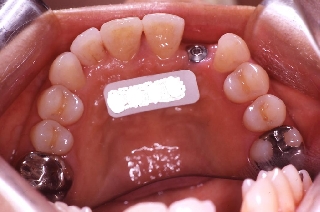

インプラント治療の為の矯正治療症例2

初診時年齢52歳。上顎前歯部欠損部インプラント治療前の咬合改善目的に来院。

当院にて前歯部の被蓋の改善を行った。

インプラント治療は専門医にて行った。

上顎 上顎 上顎